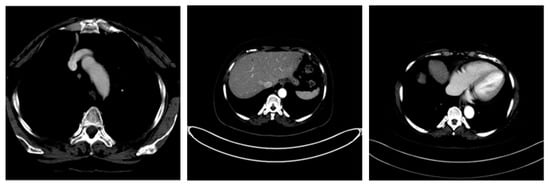

| Image Number | Overlaid Image | Deep Lesion Label | CNN Result | Clinical Radiologist’s Diagnosis | Grad-CAM Helpfulness |

|---|---|---|---|---|---|

| 1 | ![]() | Has Tumor | Has Tumor | Has Tumor | Some |

| 2 | ![]() | Has Tumor | Has Tumor | Has Tumor | Yes |

| 3 | ![]() | Has Tumor | Has Tumor | Has Tumor | Yes |

| 4 | ![]() | Has Tumor | Has Tumor | Has Tumor | Yes |

| 5 | ![]() | Has Tumor | Has Tumor | Has Tumor | Yes |

| 6 | ![]() | No Tumor | Has Tumor | Has Tumor | Yes |

| 7 | ![]() | Has Tumor | Has Tumor | Has Tumor | Yes |

| 8 | ![]() | Has Tumor | Has Tumor | Has Tumor | Yes |

| 9 | ![]() | Has Tumor | Has Tumor | Has Tumor | Some |

| 10 | ![]() | Has Tumor | Has Tumor | Has Tumor | Yes |

| 11 | ![]() | Has Tumor | Has Tumor | No Tumor (Cyst) | Some |

| 12 | ![]() | Has Tumor | Has Tumor | Has Tumor | Yes |

| 13 | ![]() | Has Tumor | Has Tumor | No Tumor | Yes |

| 14 | ![]() | Has Tumor | Has Tumor | No Tumor (Inflammation of the Biliary Tract) | Some |

| 15 | ![]() | No Tumor | Has Tumor | No Tumor (Cyst) | Some |

| 16 | ![]() | Has Tumor | Has Tumor | Has Tumor | Yes |